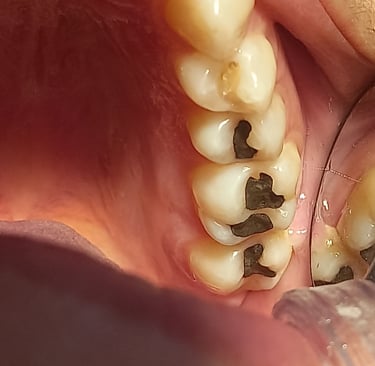

Porque trocar suas amálgamas?

Amálgama possui mercúrio, contração de dilatação diferente e causa micro trincas no esmalte dental consequentemente causando infiltrações.

A amalgama é um material restaurador utilizada na odontologia que contém mercúrio. No entanto, o uso desse material pode trazer alguns efeitos indesejáveis. Devido à sua contração e dilatação diferente em relação ao esmalte dental, isto pode ocasionar micro trincas, essas trincas, por sua vez, podem resultar em infiltrações, permitindo que bactérias e outros agentes nocivos penetrem na estrutura dentária. Esse processo pode levar à deterioração do dente e até mesmo ao surgimento de cáries. Portanto, é importante que os pacientes estejam cientes dos possíveis problemas relacionados ao uso de amalgama e busquem alternativas mais seguras e estéticas para a restauração dental.